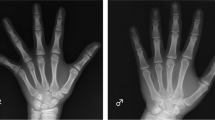

The process of growth and maturation of long (radius and ulna) and short (metacarpals and phalanges) bones of the hand (enchondroplasia) differs from that of the carpal cuboid bones (chondral osteogenesis). This study aimed to assess the impact of growth hormone (GH) on these two processes of bone maturation.

Subjects of the study were 95 prepubertal children: 30 children with GH deficiency and 65 children with idiopathic short stature, aged 7.4 ± 1.9 y (mean ± SD) (trial registration number 98-0198-033). Bone maturation was assessed by the Greulich and Pyle method from X-rays obtained at the start and at 1 and 2 y of GH treatment, separately for carpals, long bones, and short bones, and was expressed as years of delay relative to chronological age.

The dominant effect of GH was on chondral osteogenesis, with milder effect on enchondroplasia. A distinct delay in carpal and long-bone maturation, which normalizes during 2 y of GH treatment, was typical in GH-deficient children. Therefore, separate carpal bone assessment in bone age reading is needed.